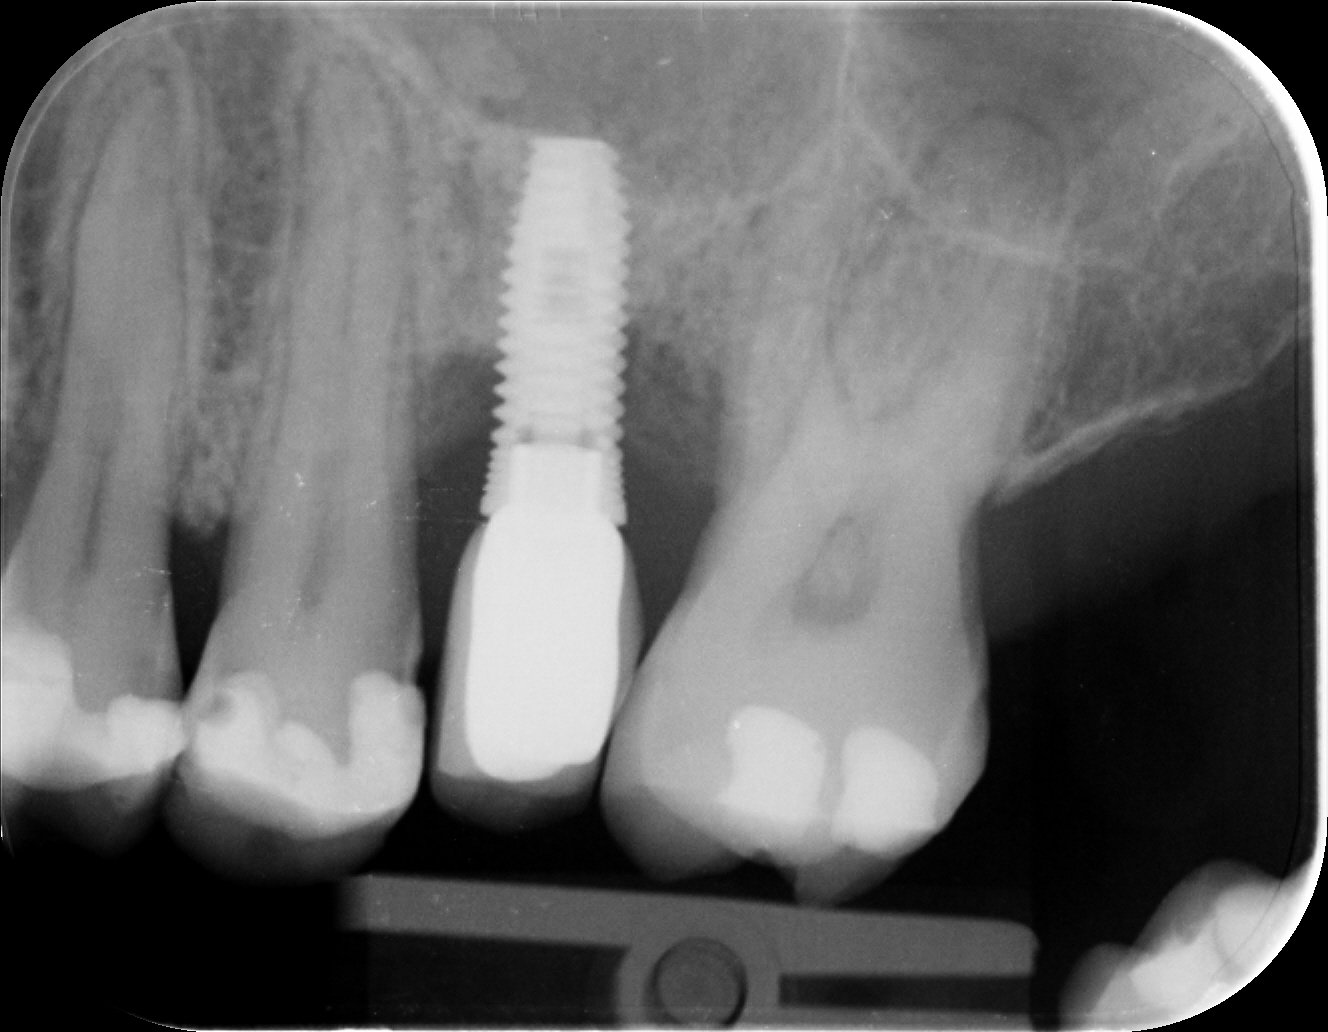

alguien puede decirme que implante es el posicionado mas o menos a la altura de la p.14? viene con el de otra clínica y nos gustaría poder contar con el [...]

Quisiera saber conexion o si es posible marca y modelo de este implante Gracias